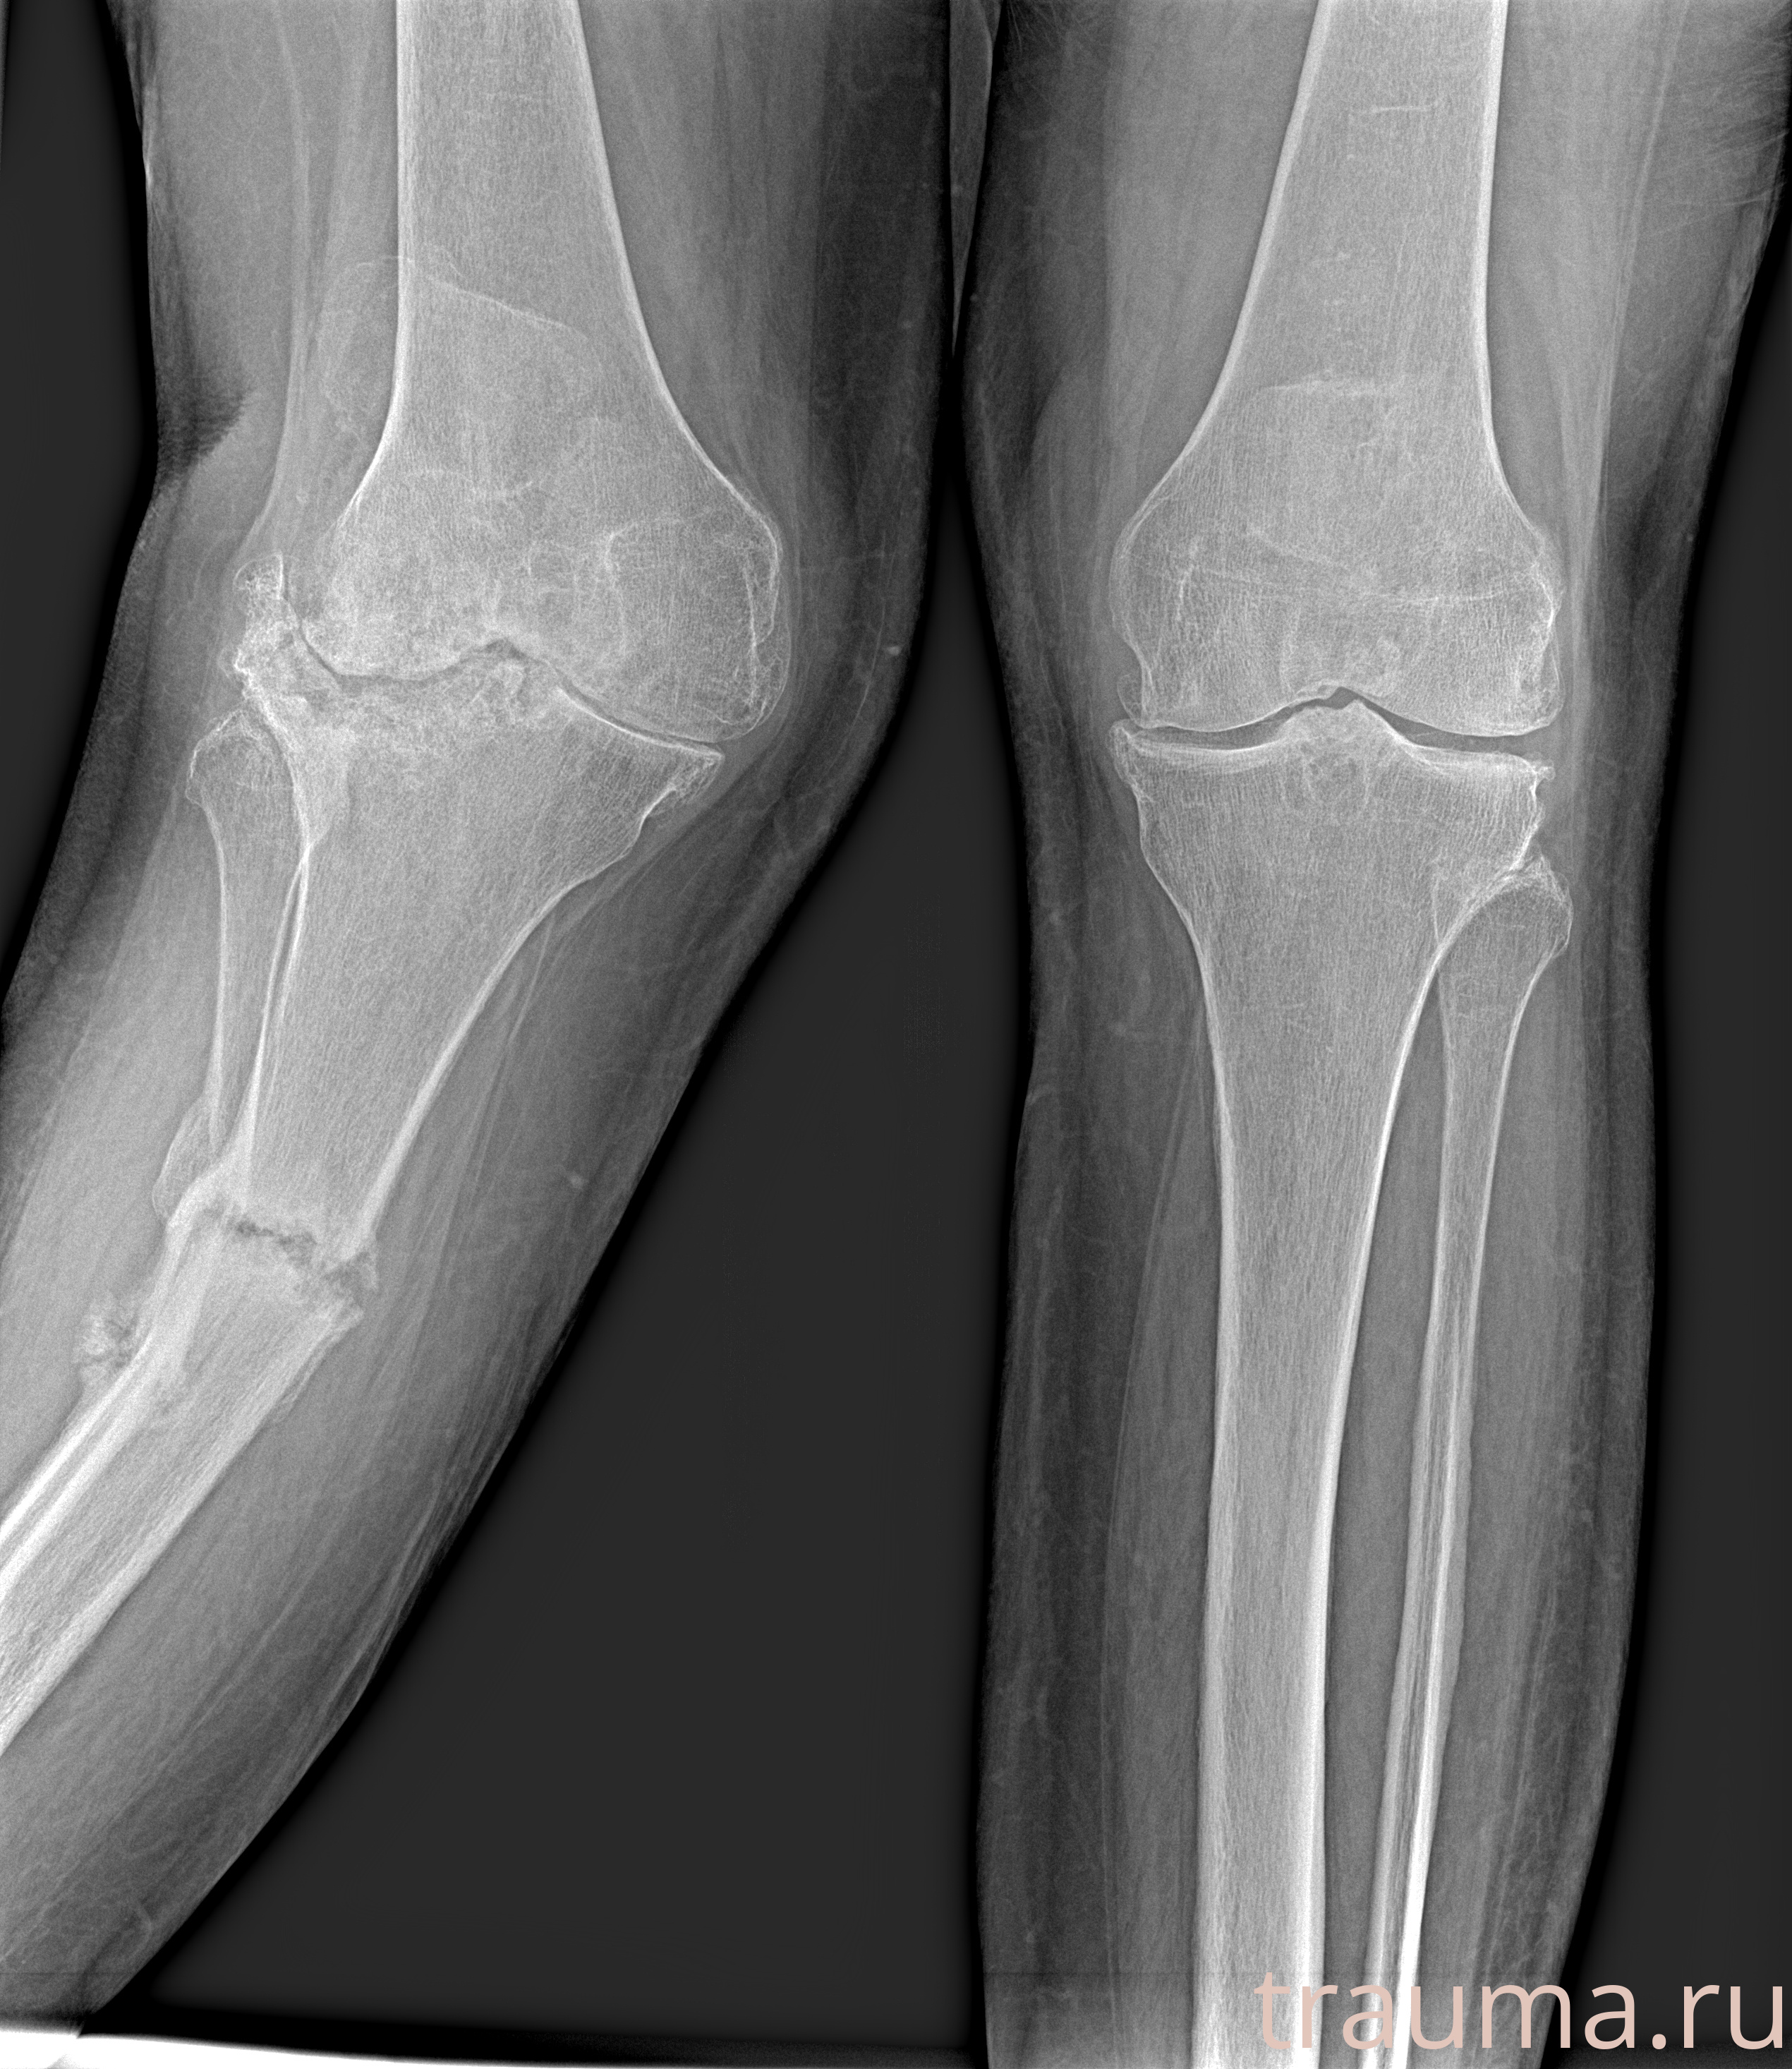

Рентгенограммы

Рентген на дому: по вашему адресу приезжает врач-рентгенолог, травматолог-ортопед с мобильным рентгеновским аппаратом, проводит диагностику травмы или заболевания, делает необходимые рентгенограммы, дает рекомендации по дальнейшему лечению. Получить качественные снимки в домашних условиях возможно благодаря уникальной методике, разработанной МосРентген Центром для института  Склифосовского